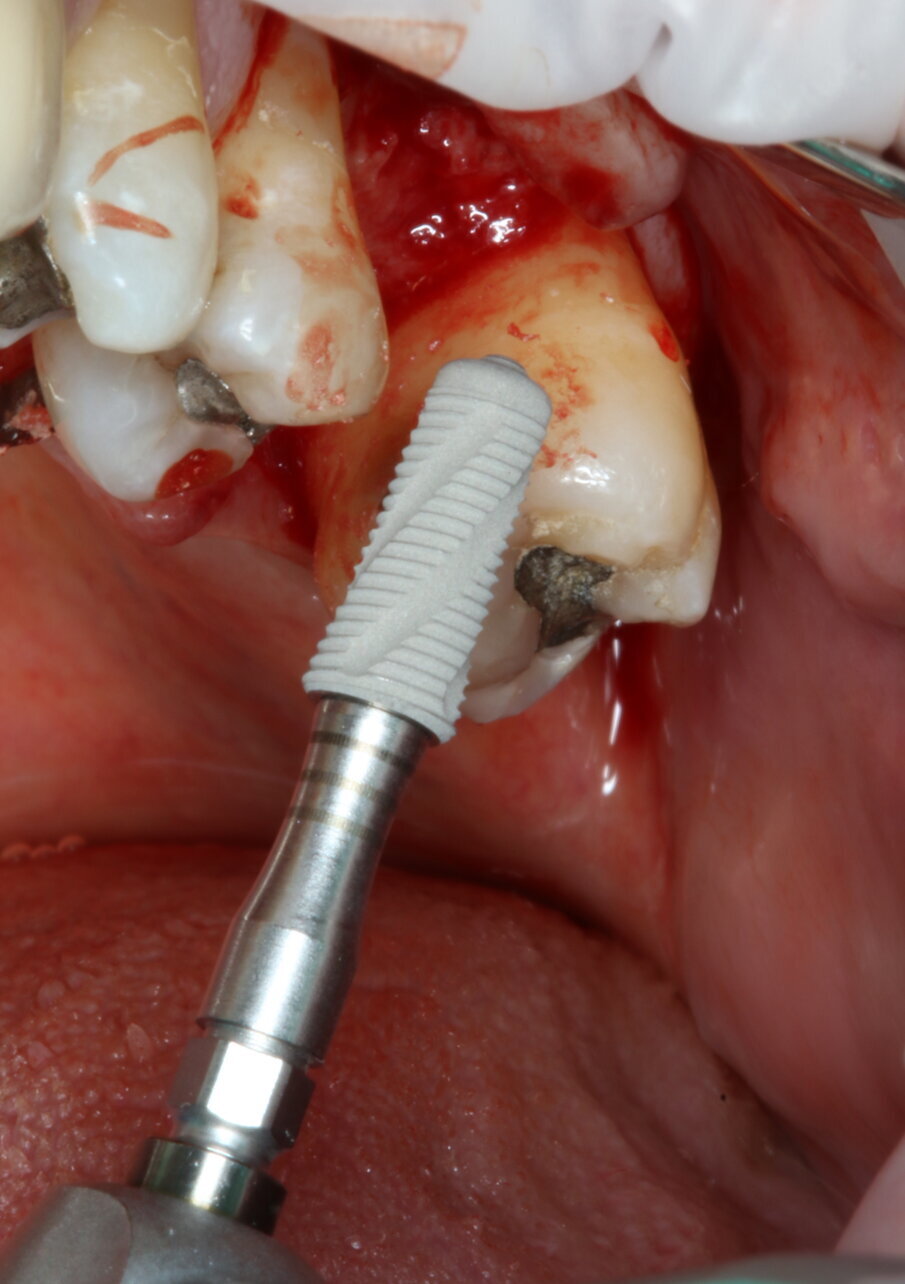

Posizionamento implantare

È stato inserito un impianto tronco-conico di 10 mm di lunghezza e 4,2 mm di diametro (AoN SLC con connessione Revcon) con torque di inserzione di 35 N e valori di ISQ pari a 66 in direzione vestibolo-linguale e 68 in direzione mesio-distale20. È stato applicato un moncone conometrico dritto e avvitato a 35 N con relativa cappa di guarigione in peek21 (Figg. 4, 5).

Fig. 4_Inserimento dell’impianto (AoN SLC con connessione Revcon).